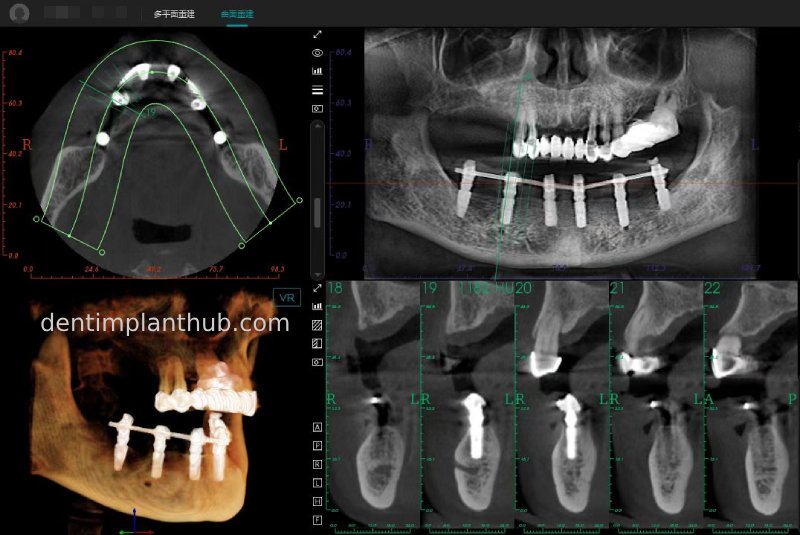

CBCT review results on 13 May '24

46

44

42

32

34

36